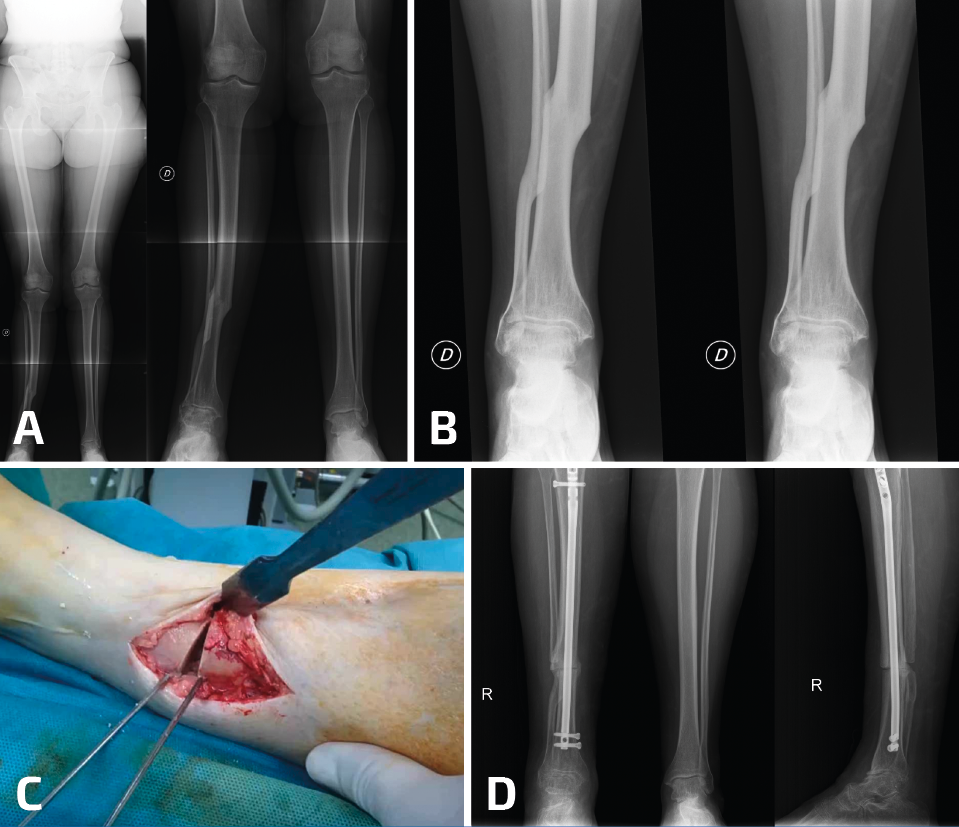

La región diafisaria de la tibia también puede presentar una desaxación como consecuencia de una consolidación viciosa de una fractura de tibia. En este escenario, la artropatía del tobillo puede mejorar de manera muy llamativa con la corrección de la deformidad proximal (Figura 2).

Figura 2. Paciente con consolidación viciosa tras fractura diafisaria de tibia tratada ortopédicamente y dolor incapacitante en el tobillo ipsilateral. A: las telerradiografías muestran una deformidad en valgo; B: la deformidad es multiplanar y la radiografía en proyección lateral nos muestra un recurvatum importante; C: se realizó una osteotomía en el CORA (center of rotation of angulation) con cierre medial y posterior, corrigiendo además la alteración rotacional; D: la fijación se consiguió con un clavo intramedular. Aunque el tobillo no estaba radiológicamente “sano”, la mejoría de la paciente fue muy notable y no ha precisado (5 años después de la corrección) cirugía adicional en el tobillo.